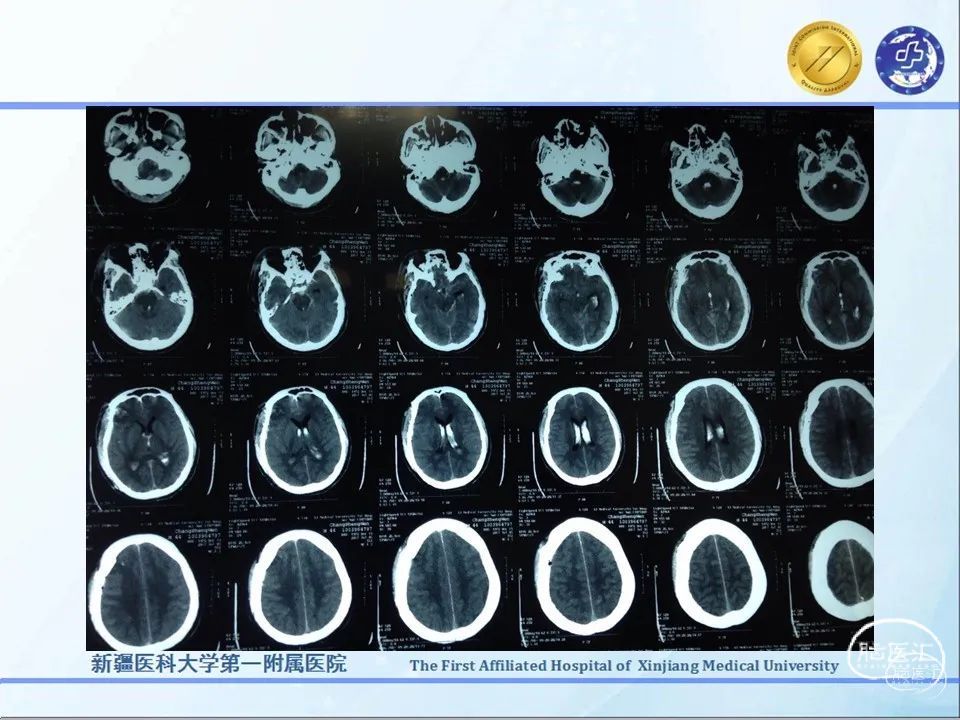

监测有道丨特重型颅脑损伤心跳呼吸骤停抢救成功一例——颅脑创伤-神经重症周刊(第235期)

今天为大家分享的是《监测有道丨颅脑创伤-神经重症周刊》第235期,由新疆医科大学第一附属医院重症医学中心王鑫副主任医师带来的:特重型颅脑损伤心跳呼吸骤停抢救成功一例,欢迎观看、阅读。